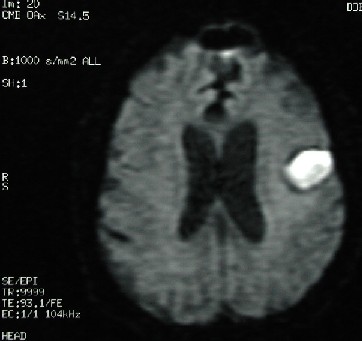

Şimdi de şu son iki MR görüntülerini inceleyelim. İlk görüntü Diffüzyon (diffusion) görüntüleme ve 2. ise "diffusion coefficient" (ADC) görüntülemedir. Tanınız Nedir?

2- Diffüzyon görüntüleme tekniği kullanıldığında intrakraniyal kanama serebral infarkt ile karışabilir. Diffüzyon görüntüleme tekniğinin bu vakada çok fazla tanısal degeri yoktur; ancak kanama çevresindeki beyin dokusunda iskemik alanları tesbit etmede faydalı olur.

MR Diffüzyon görüntüleme de hiperintens olarak görülen lezyonlar şunlardır: akut "stroke", epidermoid, "pyogenic" infeksiyon, herpes encephalitis, Creutzfeldt-Jakob sendromu, çoğu diffüz "axonal injury", oxyhemoglobin, extracellular methemoglobin ve bazı MS lezyonları